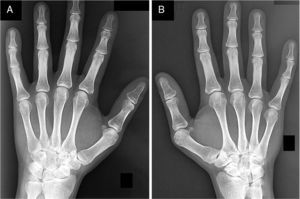

We report the case of a 34-year-old male diagnosed with RF positive polyarticular JIA at 15 months of age, based on symmetric polyarthritis affecting elbows, wrists, metacarpophalangeal and proximal interphalangeal joints on the hands, as well as the knees, ankles and metatarsophalangeal joints and subcutaneous nodules, positive for RF (353IU/ml) and elevated acute phase reactants (erythrocyte sedimentation rate of 45mm/h, C-reactive protein 6.5mg/l). He had no other relevant family or personal history. He was treated with nonsteroidal antiinflammatory drugs, systemic and intra-articular corticosteroids, gold salts and methotrexate but, despite this, the disease remained active with persistent synovitis of both wrists, developing bilateral subluxation at that level and limitation of dorsiflexion and supination. Radiographs of both wrists showed shortening of the medial distal radius, exaggeration of the radial tilt and proximal migration of the bones of the first row of the carpus, adopting a V shape between the radius and ulna, consistent with Madelung's deformity (Fig. 1). The patient also developed “trigger fingers” in both hands and bilateral hallux valgus. At age 24, he began treatment with etanercept, achieving control of disease activity. Currently no synovitis of the wrists is present, but the limited movement persists, though it does not prevent him from carrying out his usual activities.

Among the clinical and radiological characteristics of Madelung's deformity, dorsal and medial curvature of the distal radius, an increase in the inclination of the joint surface of the distal radius, the triangulation of the carpus with proximal migration and volar migration of the semilunar bone, as well as the prominent ulnar head, are common.8 This deformity is typically present bilaterally and manifested before 20 years of age. Patients have a limited pronation and supination of the affected carpus.3,5 Severe cases develop progressive osteoarthritis and instability of the distal radioulnar joint, radiocarpal osteoarthritis and may complicate with rupture of the extensor tendons of the fingers.3